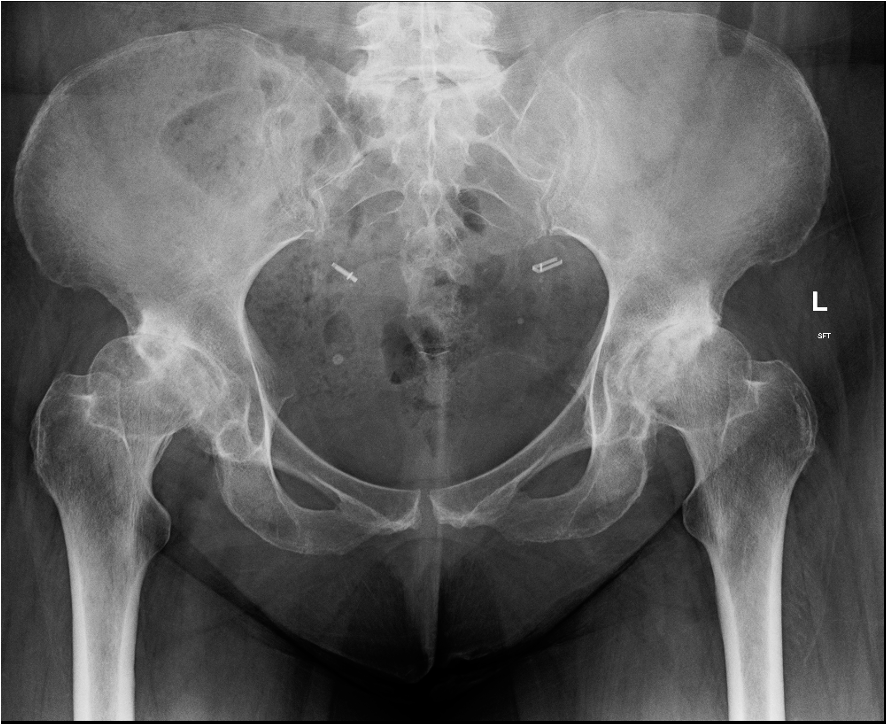

Crowe Classification

| Crowe Type | Definition |

|---|---|

| I | Subluxation < 50% vertical diameter femoral head |

| II | Subluxation 50 - 75% vertical diameter femoral head |

| III | Subluxation 75 - 100% vertical diameter femoral head |

| IV | Proximal migration of > 100% vertical diameter femoral head |

Crowe I

Crowe II

Crowe III

Crowe IV